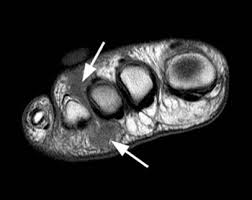

Если заболевание находится на ранних стадиях развития, и уплотнение на стопе не имеет особой выраженности, пациента отправляют на прохождение более детальных медицинских обследований – МРТ ноги или рентгенографическое, чтобы исключить такие болезни, как артрит, либо перелом, так как они имеют схожую симптоматику.

Неврома Мортона на МРТ.